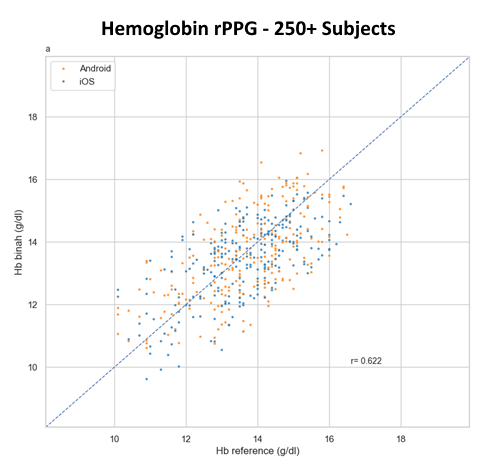

Briah.ai’s technology can measure blood pressure, heart rate, heart rate variability, respiration rate, hemoglobin, and hemoglobin A1C.

How accurate are the measurements provided by Briah.ai?

Our technology meets high accuracy standards and has been validated through extensive research and testing.